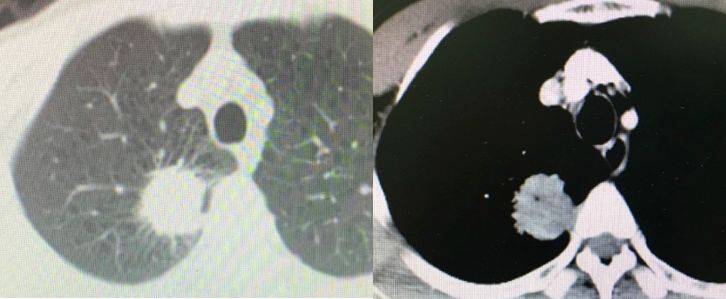

胸部增强CT(2019.01.18)

右肺上叶胸膜下软组织密度结节影,与胸膜关系紧密,最大截面积约3.5cm×3.3cm,考虑肿瘤性病变。

图2. 胸部增强CT(2019.01.18)